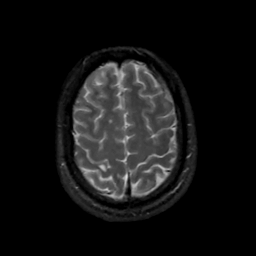

MR Study #14, June 2, 1991 -- Slice #41

[Home][Help][Clinical][Tour 1][Tour 2] Slice 41